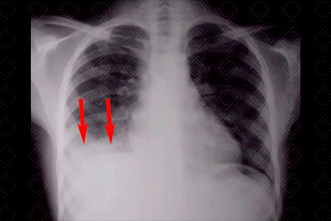

Texto alternativo para a imagem Figura 1. Créditos: Dra. Elazir Mota - Rio de Janeiro/RJ

Descrição da figura 1: Radiografia de tórax evidenciando opacidade na base pulmonar direita (setas vermelhas), apagando o contorno diafragmático deste lado. Tratava-se de uma paciente jovem, com relato de pneumonias de repetição há cerca de 2 anos. O corpo estranho foi suspeitado tardiamente e evidenciando durante broncoscopia.

• Radiografia de tórax: A radiografia de tórax pode ser normal, mas em boa parte dos casos apresenta sinais indiretos: hiperinsuflação pulmonar do lado acometido ou pode haver a presença de alguma opacidade pulmonar (atelectasia) . Na maioria dos casos, o corpo estranho causa uma obstrução parcial do brônquio, funcionando como mecanismo valvular, ou seja, o ar entra e tem dificuldade para sair, levando a hiperinsuflação. Já nos casos de obstrução total, observaremos atelectasias ( figuras 1 e 2 ) ;